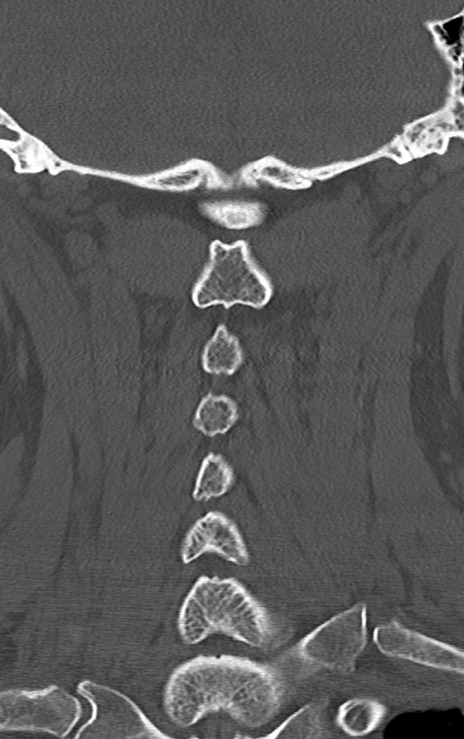

頚椎CT

矢状断像